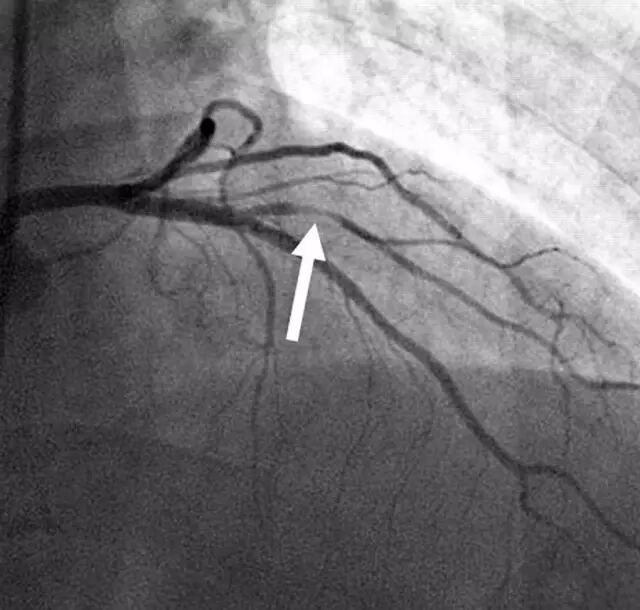

第三步:血管造影

在一路抵达目的地的过程中,医生需要通过 X 光透视来观察情况,也需要通过导管推入「造影剂」,在 X 光下清楚显示血管,找到病变部位。